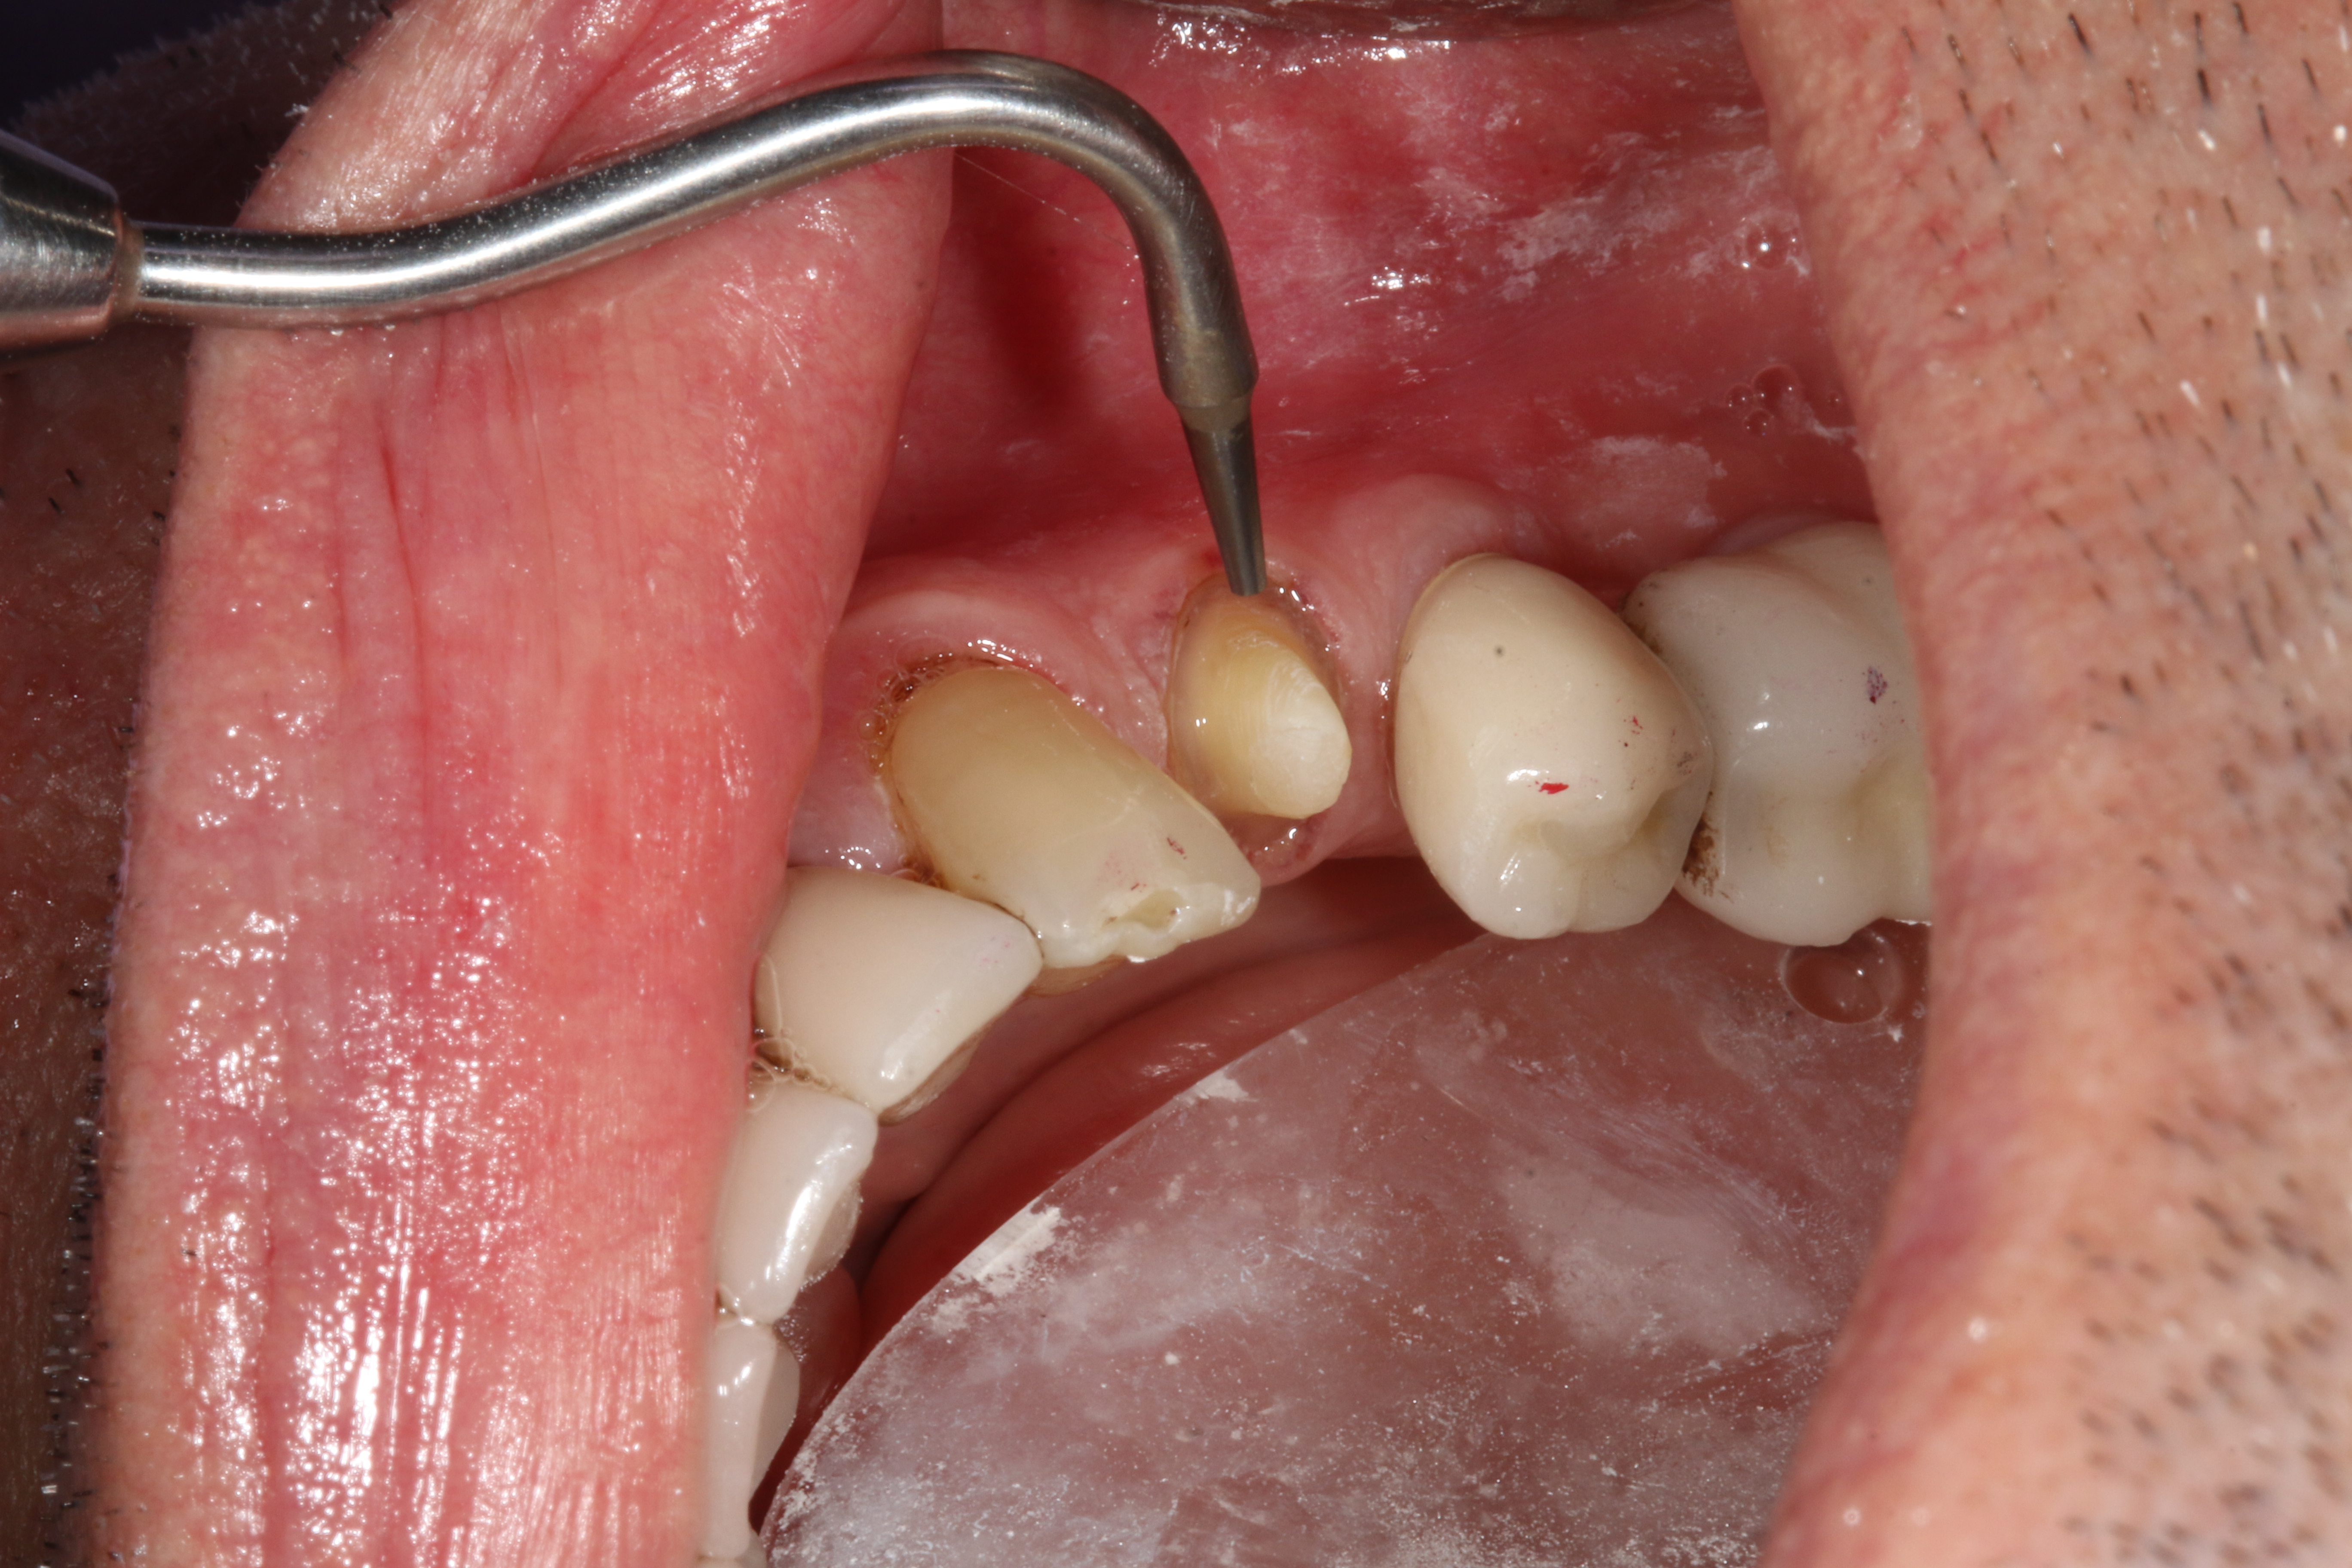

A 71-year-old man presented with acute pain in tooth No. 29 that was spontaneous, unresponsive to vitality testing, and sensitive to percussion. He was referred to an endodontist for treatment of acute apical periodontitis due to the non-vitality of the nerve. Because of the multiple restorations and lingual decay of the tooth, enamel and dentin were compromised, causing the tooth to be biomechanically at high risk and requiring an eventual post-and-core and crown (Figure 1 and Figure 2). Endodontic care included nonsurgical intracanal therapy and creating room for a post space.

Fig 1. Multiple restorations decrease enamel and dentin strength, requiring full-coverage enhancement.

Figure 1

Fig 2. Preoperative view of tooth to be restored shows defective Class 5 restoration that unfortunately was mirrored on the lingual gingival margin.

Figure 2